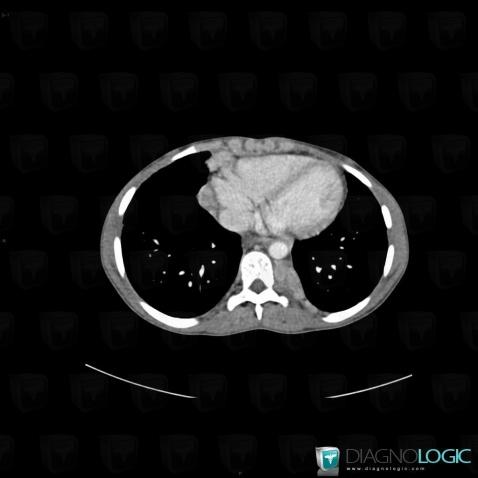

Sarcoïdose, Médiastin, Scanner

Voici les informations spécifiques à l'image clé ci dessus:

- Diagnostic Sarcoïdose, Localisation(s) Médiastin, comportant les gammes Masse médiastinale moyenne